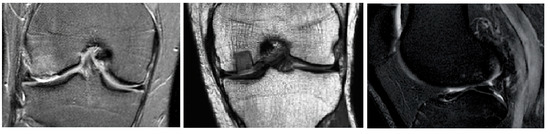

4.3. Early Signs of Articular Cartilage Classification

This section brings the most interesting results for the clinical evaluation of articular cartilage as a classification of early signs of osteoarthritis, which manifest as cartilage loss. This is substantially important to distinguish these cartilage features from those of healthy cartilage with compact structure, which is usually represented by a homogenous MR signal. On the other hand, cartilage loss is standardly represented by intensity variations and a weaker MR signal when compared with healthy cartilage (Figure 12). In order to classify such early signs of cartilage loss from the healthy cartilage structure, we used two convolutional neural networks (CNNs): GoogLeNet and ResNet 18, with various hyperparameter settings to find the best alternative for the cartilage loss classification. For this classification, we used the segmentation data of articular cartilage based on the proposed clustering scheme with a genetic algorithm. This alternative is used due to its best performance, as we declared in the previous section. We performed segmentation for 1000 MR images in total, which were equally divided into 500 healthy images and 500 images with early cartilage loss. As an example of the segmentation based on the genetic algorithm-based clustering, we show the closed segmentation curve, which outlines a part of the cartilage area (healthy cartilage) where other parts of the segmentation model are eliminated.

Figure 12. Examples of detection tibial (left) and femoral (right) articular cartilage by GA-based clustering, where the blue squares indicate the spots of early cartilage loss.

We built the classification analysis based on the segmentation results, which we present in Figure 12. We selected two types of convolutional neural networks, GoogLeNet and ResNet 18, to show a comparative analysis of the classification performance to recognize early cartilage loss. We studied the classification performance within various hyperparameter settings, including various number of epochs and the ratio of the training/validation dataset. The tested hyperparameters are summarized in Table 8. We used the same parameters for both CNNs to achieve comparable results. The entire classification procedure for the recognition of cartilage loss is depicted in Figure 13.